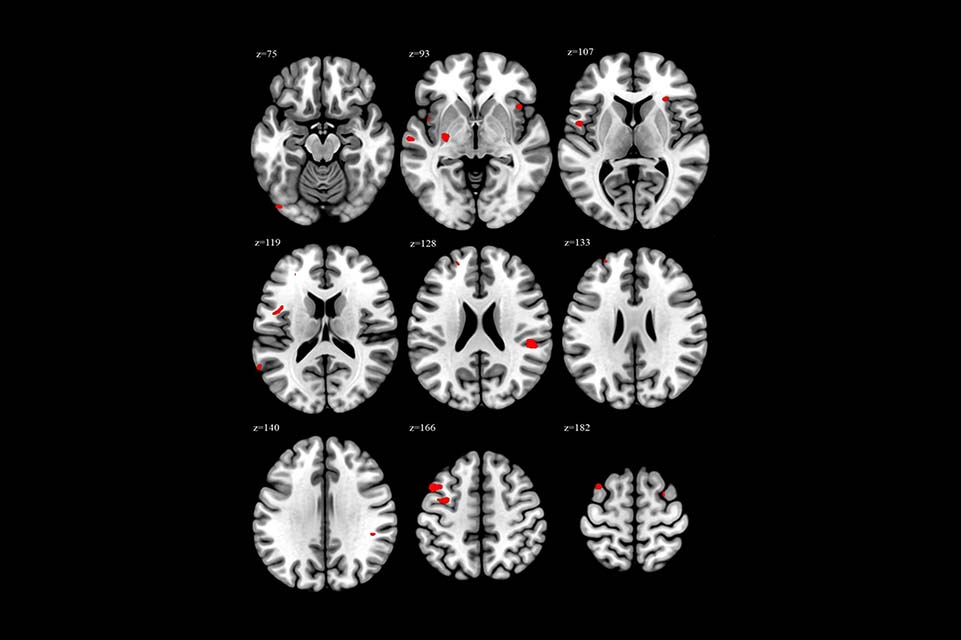

Share Twitter Facebook LinkedIn Email It can potentially affect how people think, manage emotions, and handle stress.Read More